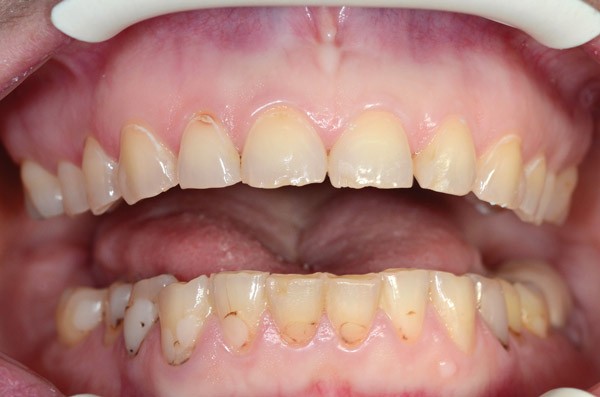

À l’examen clinique (fig. 2 à 4), on observe :

– l’absence de 17, 27 et 47 (suite de lésions carieuses volumineuses) ;

– un parodonte sain ;

– des érosions sévères généralisées, symétriques et bilatérales (occlusales, palatines et vestibulaires au maxillaire) ;

– des lésions carieuses débutantes de site 3 ;

– des obturations préexistantes infiltrées ;

– une vitalité pulpaire conservée sauf au niveau des prémolaires maxillaires ;

– une usure des bords libres des incisives mandibulaires